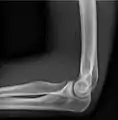

AP and lateral elbow X-ray

Projectional radiography, also known as conventional radiography,[1] is a form of radiography and medical imaging that produces two-dimensional images by X-ray radiation. The image acquisition is generally performed by radiographers, and the images are often examined by radiologists. Both the procedure and any resultant images are often simply called 'X-ray'. Plain radiography or roentgenography generally refers to projectional radiography (without the use of more advanced techniques such as computed tomography that can generate 3D-images). Plain radiography can also refer to radiography without a radiocontrast agent or radiography that generates single static images, as contrasted to fluoroscopy, which are technically also projectional.

• Soft tissues are seen with the same machine as for hard tissues, but a "softer" or less-penetrating X-ray beam is used. Tissues commonly imaged include the lungs and heart shadow in a chest X-ray, the air pattern of the bowel in abdominal X-rays, the soft tissues of the neck, the orbits by a skull X-ray before an MRI to check for radiopaque foreign bodies (especially metal), and of course the soft tissue shadows in X-rays of bony injuries are looked at by the radiologist for signs of hidden trauma (for example, the famous "fat pad" sign on a fractured elbow).

• Elbow - AP and Lateral. Radial head projections available on request